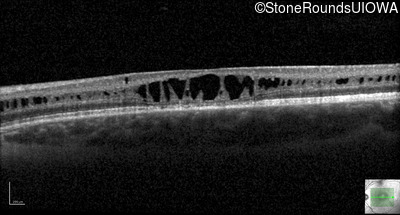

Optical Coherence Tomography - Right - 20/63 -2

Exemplar / OCT Stack

OCT Stack